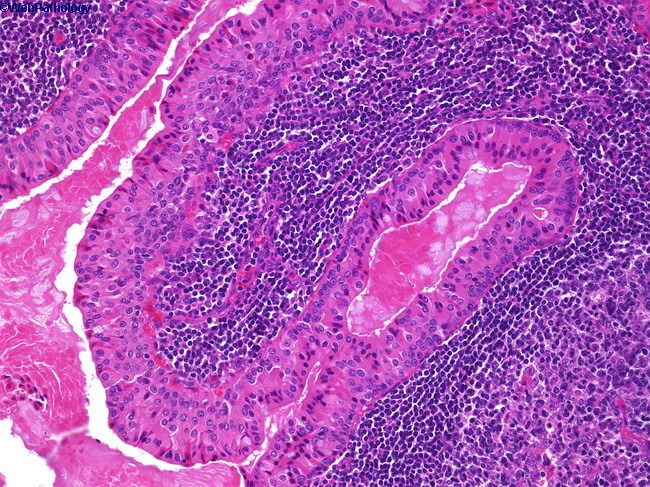

What would you expect to see on microscopic examination of the parotid tumor shown below?

This is a pleomorphic adenoma, characterized by stromal (cartilage) and epithelial (glands) tissue.